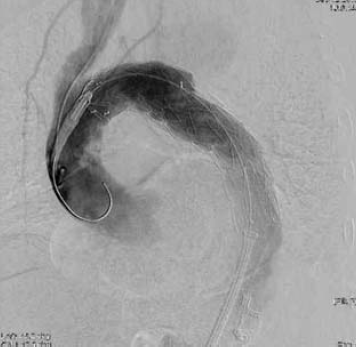

7. ábra.

III típusú endoleak után kialakult álaneurysma miatt nyitott stentgraft altávolítás és aortoaorticus graft interpositio utáni kontroll angiogram.

Jól látható a bal subclavio-caroticus transpositio.

Az egyik szemére megvakult nőbetegnél extraperitonealis iliaca feltárás hegében hasfali sérv képződött, ami hasfali reconstructiot igényelt. A hepatitis vírushordozó nőbetegnél 18 hónappal a stentgraft beültetése után az aneurysma zsák lassú, kisfokú növekedését észleltük, benne kis kontrasztanyag halmozódással. A thrombocyta aggregatio megszüntetése után 3 hónappal nyitott intercostalis ágakból további telődést –"endoleak"- et, lassú, további expansiot igazoltunk. Ismételt CTA után döntöttünk újabb, nyitott beavatkozásról. Egy férfibeteg 90 mm átmérőjű distalis aortaív álaneuryma miatt került bal a. subclavia transpositiora, illetve stentgraft beültetésre. A beültetés során az aortaív durva mészfelrakódása ék alakú benyomatot képezett a grafton, ami ballonos tágítást tett szükségessé. A friss angiographia nem mutatott endoleaket. A sorozatos CTA ellenőrzés 8 hónappal a beültetés után az aneurysma lassú növekedését mutatta és az említett meszes carina szintjén kicsiny, II-es típusú áteresztést igazolt. A vizsgálat a graft fémvázának törését mutatta. A beteg thrombocyta aggregatio gátló kezelését megszüntettük, remélve az endoleak spontán záródását. A beteget újabb ellenőrzésre visszarendeltük, de nem jelentkezett. 3 hónap múlva a nyak bal oldalán áttört, alvadékkal elzárt sipollyal került ismét látóterünkbe, ami a friss CTA szerint a jelentősen megnövekedett, mintegy 12 cm átmérőjű álaneurysmára vezetett. Azonnal műtétre vittük, amelynek során a femorofemoralis bypass és moderalt hypothermia védelmében az endograftot eltávolítottuk, a hatalmas alvadék tömeget kiemeltük és aorto-aorticus graft interpositiot végeztük. A beteg zavartalanul gyógyult, nyaki sipolya záródott. Ismételt ellenőrzésre 5 hónap múlva panaszmentesen jelentkezett.